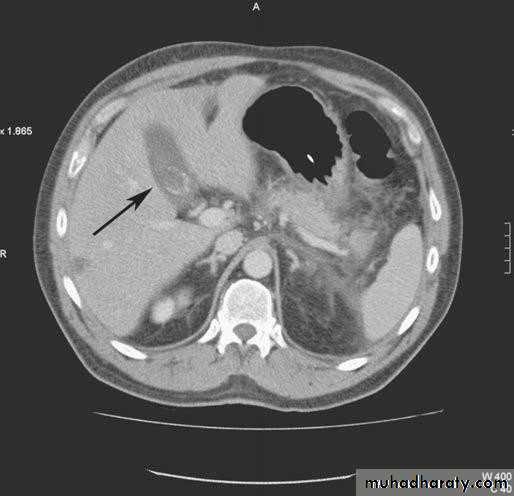

• Computerized Tomography scan;• limited usefulness in investigating the biliary tree

• Only when there is a possibility of cancer of gall bladder or bile ducts

• Use of CT scan is an integral part of the differential

• diagnosis of obstructive jaundice

• CT SCAN

• Computed tomography scan demonstrating a gallstone

• within the gall bladder (arrowed).• Magnetic Resonance Cholangiopancreatograph: